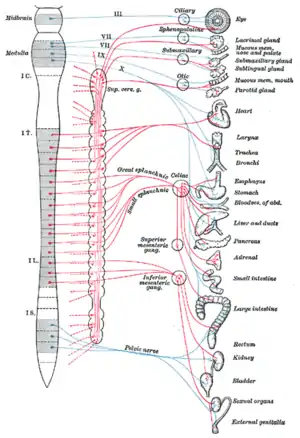

Autonomic nervous system innervation | |

The autonomic nervous system (ANS), formerly referred to as the vegetative nervous system, is a division of the nervous system that operates internal organs, smooth muscle and glands.[1] The autonomic nervous system is a control system that acts largely unconsciously and regulates bodily functions, such as the heart rate, its force of contraction, digestion, respiratory rate, pupillary response, urination, and sexual arousal.[2] This system is the primary mechanism in control of the fight-or-flight response.

Structure

The autonomic nervous system has been classically divided into the sympathetic nervous system and parasympathetic nervous system only (i.e. exclusively motor). The sympathetic division emerges from the spinal cord in the thoracic and lumbar areas, terminating around L2-3. The parasympathetic division has craniosacral "outflow", meaning that the neurons begin at the cranial nerves (specifically the oculomotor nerve, facial nerve, glossopharyngeal nerve and vagus nerve) and sacral (S2-S4) spinal cord.

Innervation

Autonomic nerves travel to organs throughout the body. Most organs receive parasympathetic supply by the vagus nerve and sympathetic supply by splanchnic nerves. The sensory part of the latter reaches the spinal column at certain spinal segments. Pain in any internal organ is perceived as referred pain, more specifically as pain from the dermatome corresponding to the spinal segment.[13]